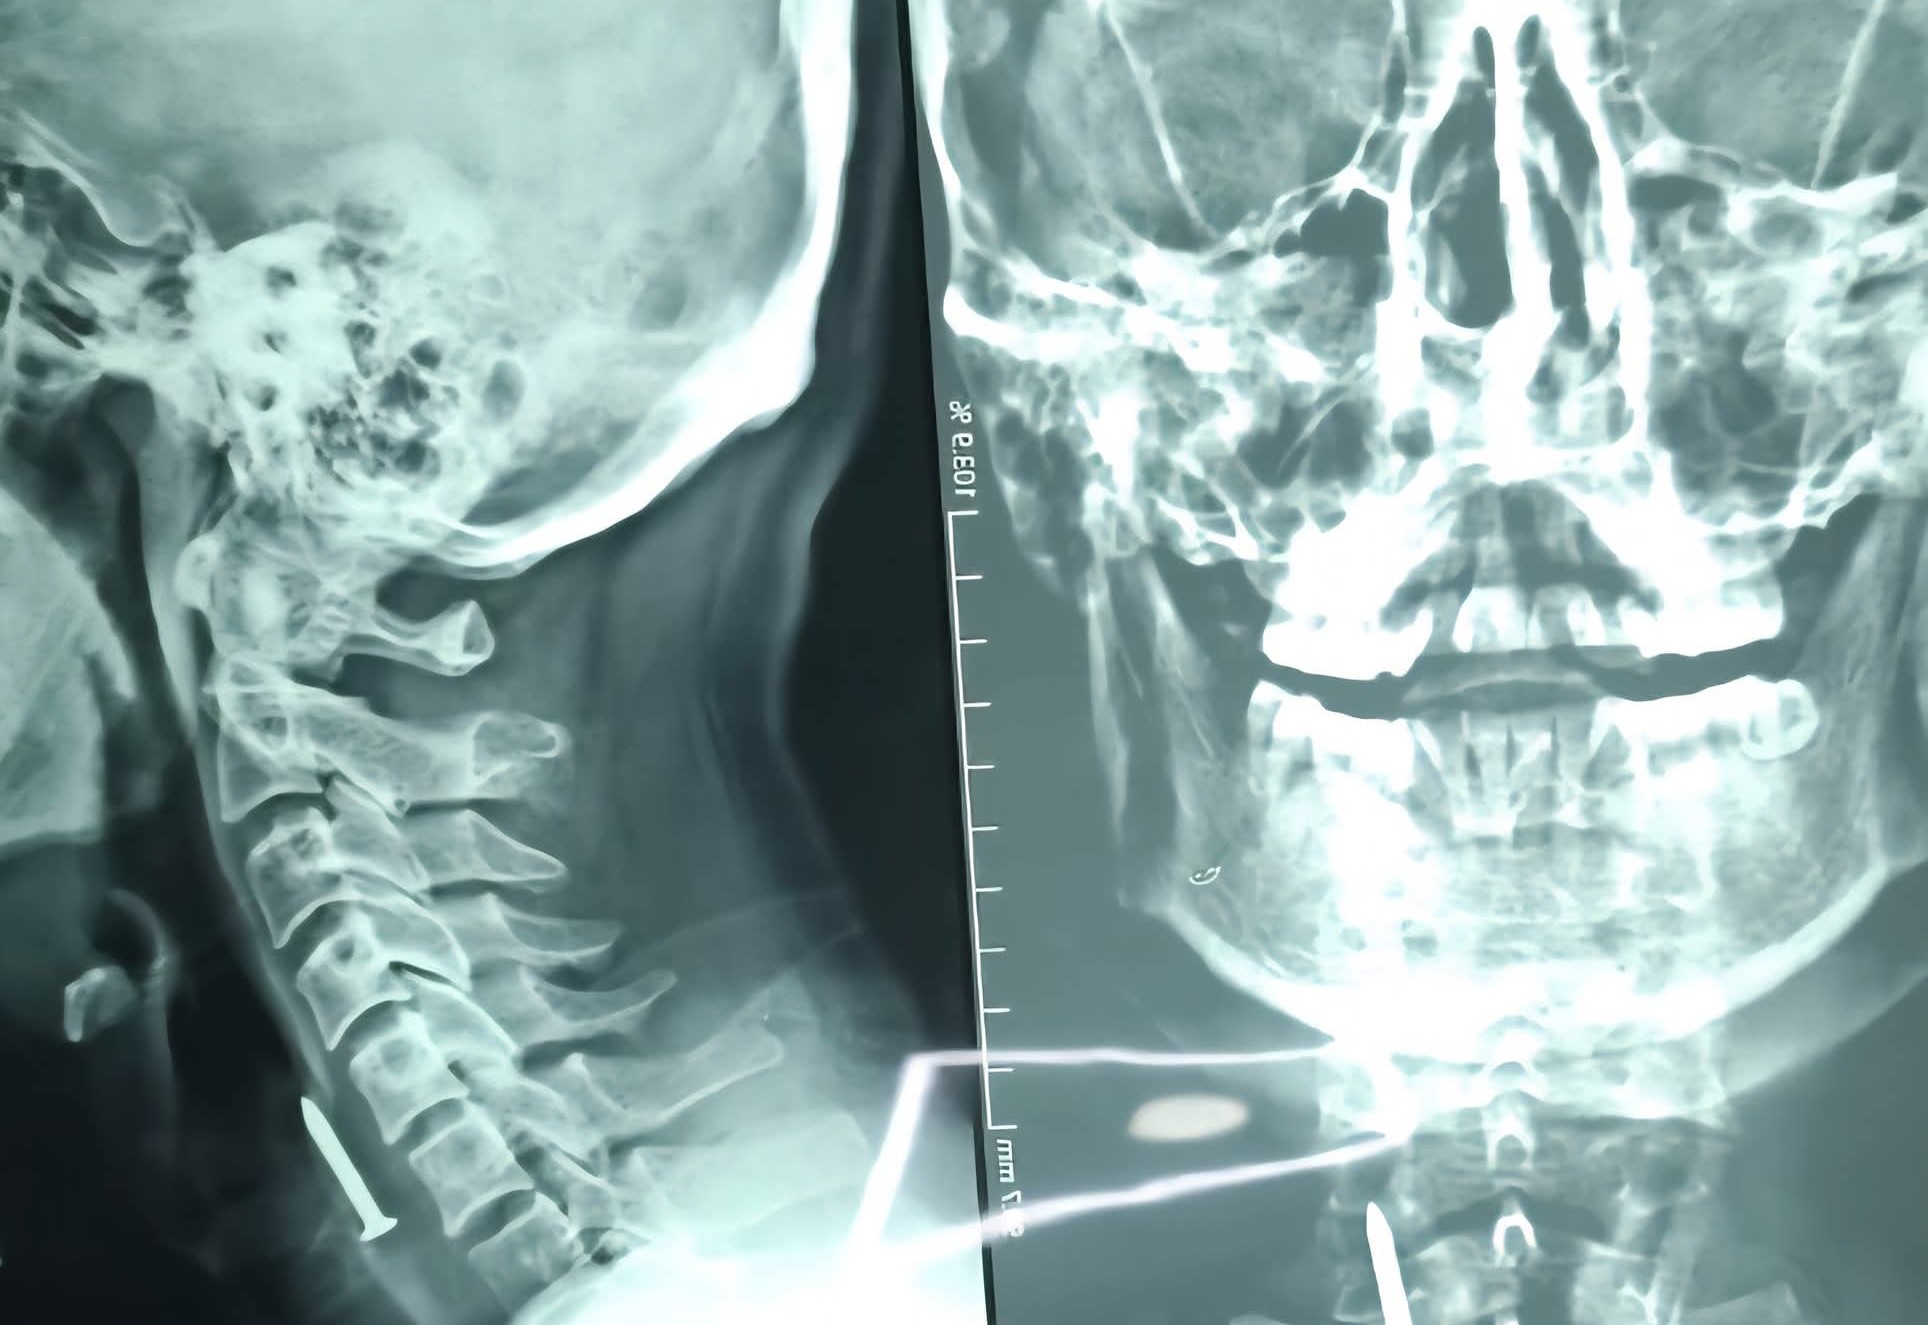

لەلایەن تیمی ئێشكگری نەخۆشخانەی كۆئەندامی هەرس و جگەری فێركاری لە شاری سلێمانی بزمارێك لە گەرووی چارەخوازێكی تەمەن 36 ساڵ دەرهێنرا و توانرا ژیانی ڕزگار بكرێت.